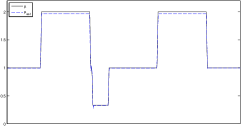

In this section, the proposed algorithm is tested on two sets of simulated two-dimensional data (with different parameter range and level of detail). We also vary the noise on the data since the reconstruction quality strongly depends on the noise level.

The data (see Figures 1 and 2) was generated in the diffusion model (1.2) using self-written (linear-basis) finite element code in MATLAB. For both examples, we took and used a uniform boundary condition . The simulated data were generated on a -grid and then down-sampled (by averaging) to to avoid inverse crime. After that, Gaussian noise with different intensities (standard deviations of and of the average signal value ) was added to the data.

Reconstruction results and error profiles at different noise levels can be seen in Figures 3 and 4. In both examples, the noise-free reconstructions are very accurate and contain mostly smoothing error. In the low-noise reconstructions, due to the fact that more regularization is necessary, some of the parameter variation is underestimated. In the high-noise examples, most detail in is lost since a lot of regularization is required to get reasonable results. The fine detail in can, however, still be recovered very accurately in both examples.